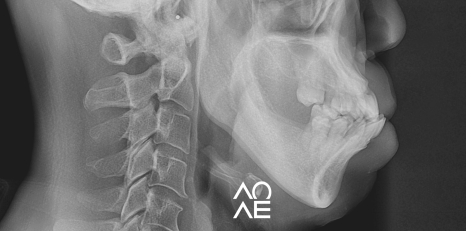

방사선 검사 등을 꼼꼼하게 진행해보니

교정이 아닌 크라운으로 치료가 가능한

구강 상태를 가지고 계셨기에 크라운 치료를

결정하고 진행하게 되었습니다.